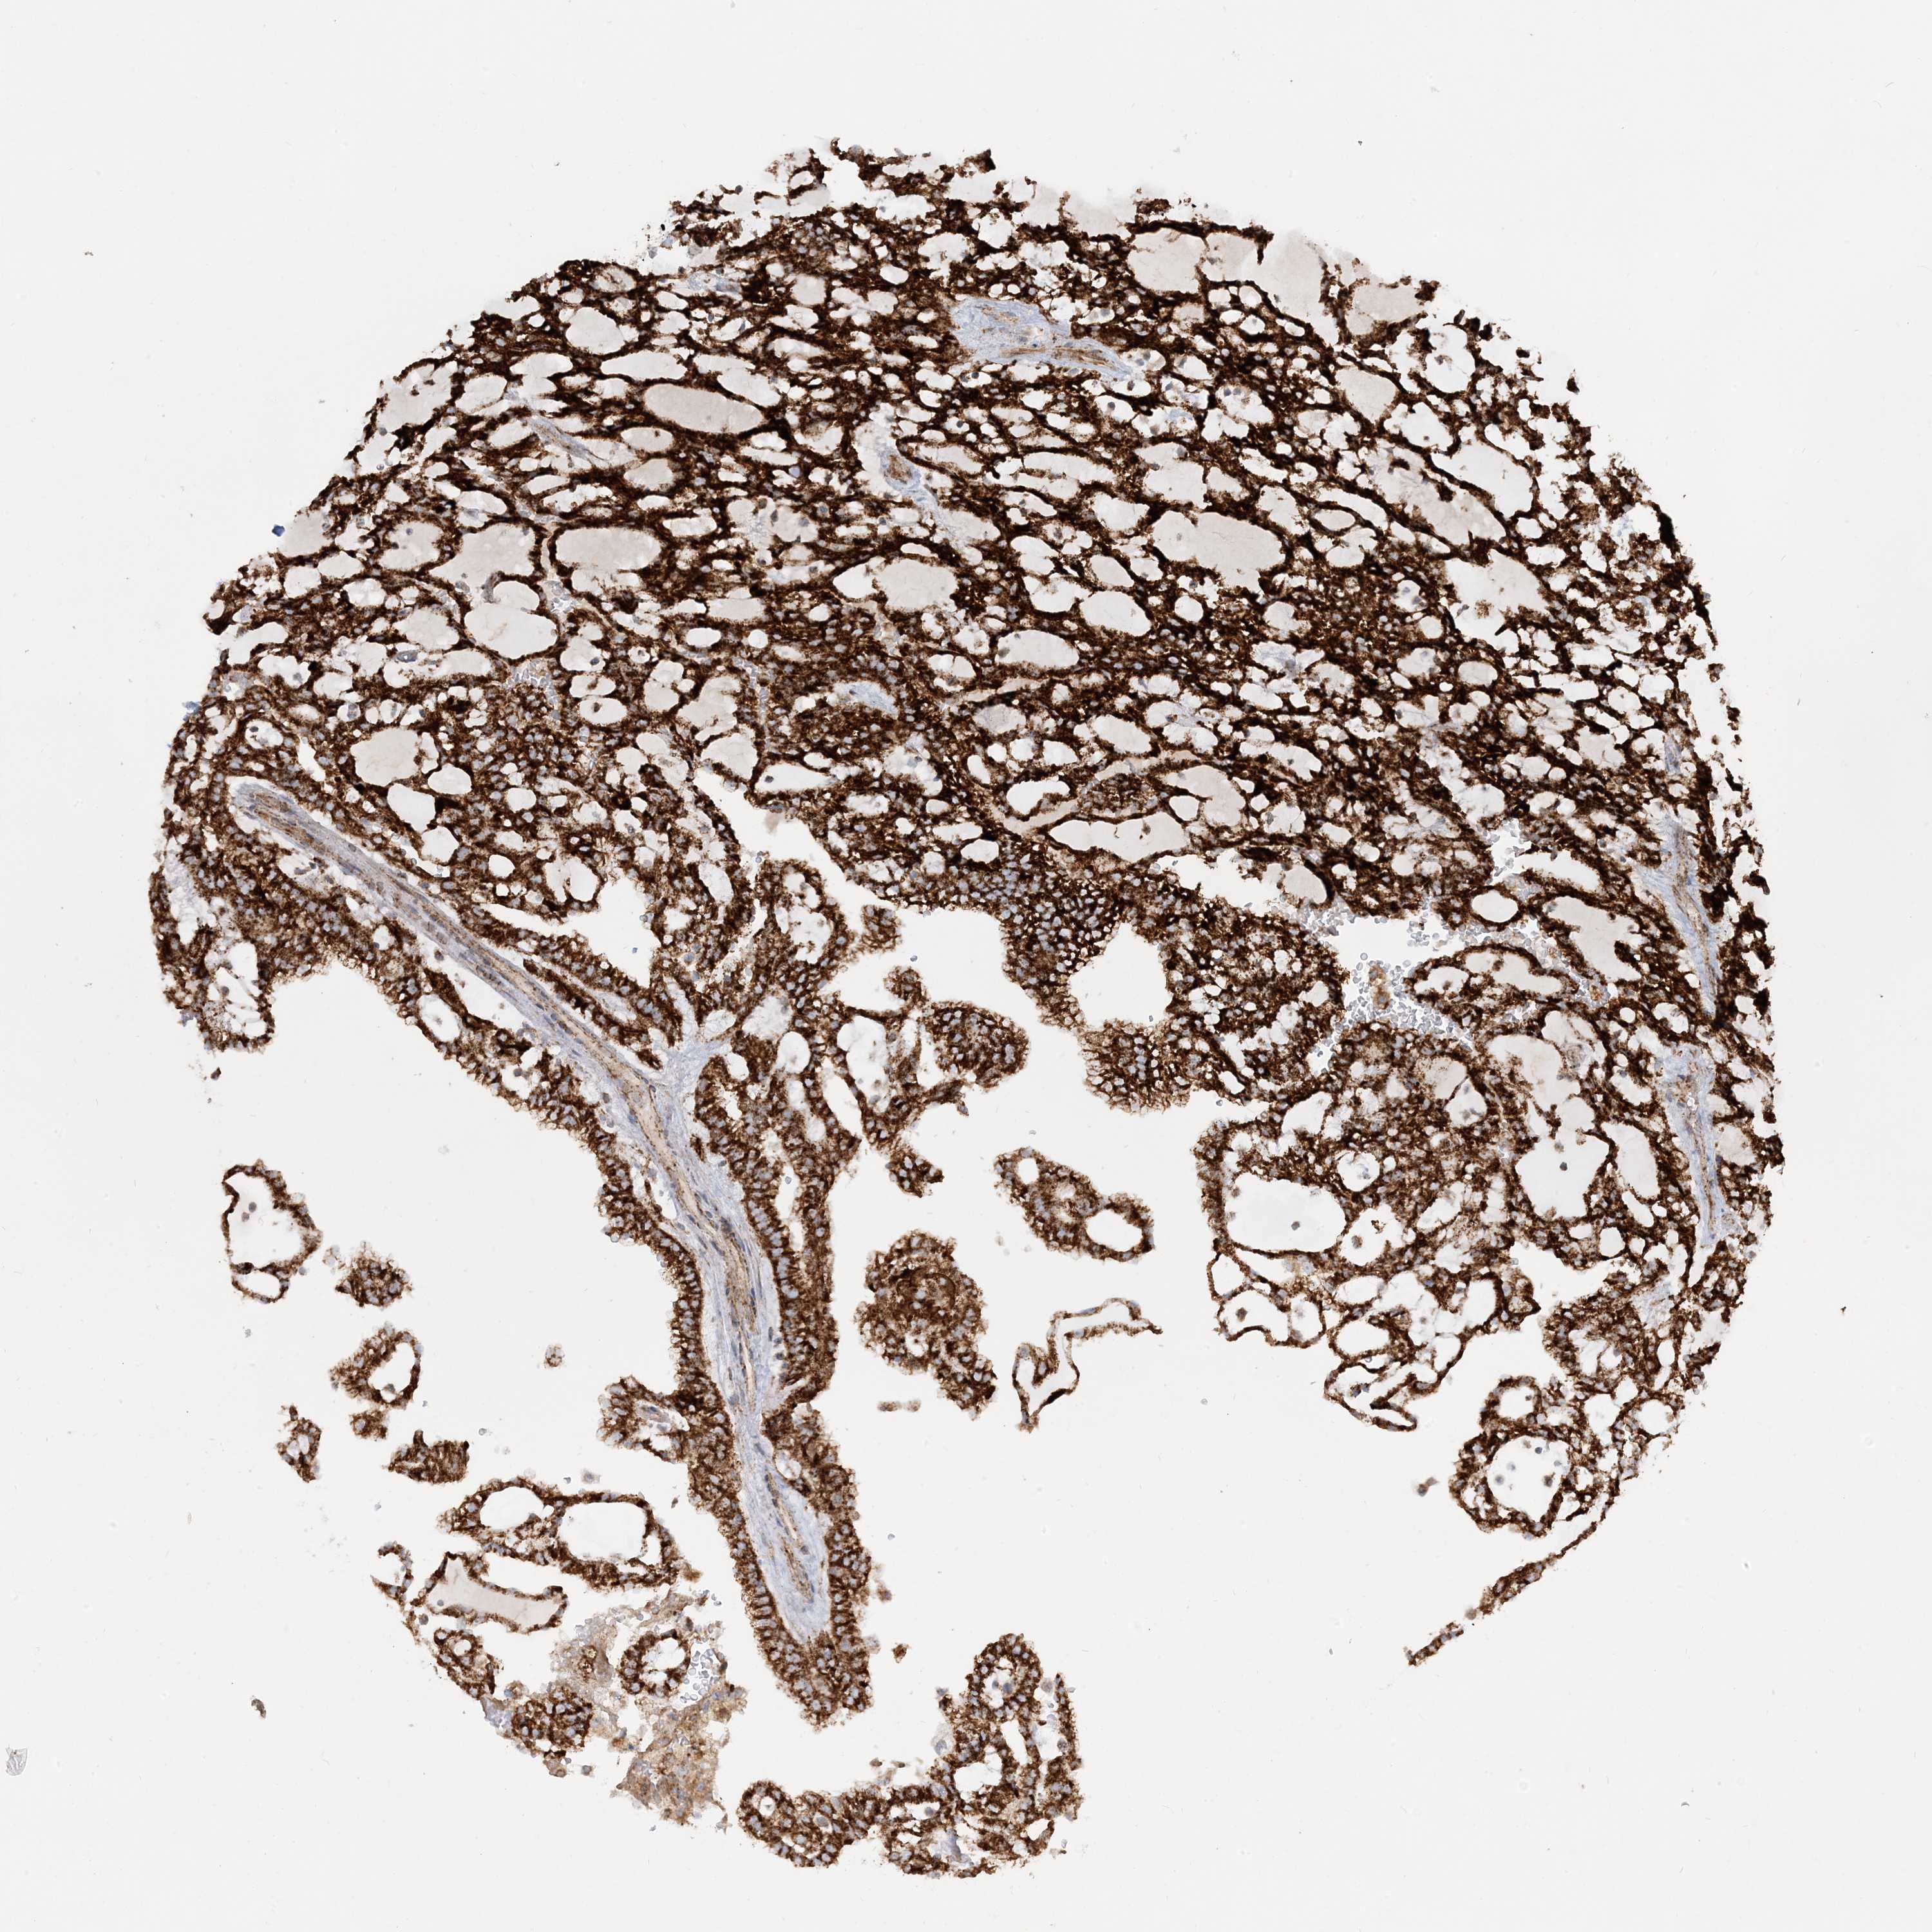

KIDNEY RENAL PAPILLARY CELL CARCINOMA (TCGA) - Interactive survival scatter ploti

The Survival Scatter plot shows the clinical status (i.e. dead or alive) for all individuals in the patient cohort, based on the same data that underlies the corresponding Kaplan-Meier plots. Patients that are alive at last time for follow-up are shown in blue and patients who have died during the study are shown in red.

The x-axis shows the expression levels (FPKM) of the investigated gene in the tumor tissue at the time of diagnosis. The y-axis shows the follow-up time after diagnosis (years). Both axes are complimented with kernel density curves demonstrating the data density over the axes. The top density plot shows the expression levels (FPKM) distribution among dead (red) and alive patients (blue). The right density plot shows the data density of the survived years of dead patients with high and low expression levels respectively, stratified using the cutoff indicated by the vertical dashed line through the Survival Scatter plot. This cutoff is automatically defined based on the FPKM cutoff that minimizes the p-score. The cutoff can be changed by dragging the vertical line or by entering a cutoff value in the square labeled "Current cut-off".

Under the Survival Scatter plot the p-score landscape (black curve; left axis) is shown together with dead median separation (red curve; right axis). Dead median separation is the difference in median mRNA expression between patients who have died with high and low expression, respectively. It is calculated as follows: median FPKM expression of dead patients with high expression - median FPKM expression of dead patients with low expression. This is intended to aid the user in visually exploring custom cutoffs and the associated p-scores and dead median separation.

Individual patient data is displayed and can be filtered by clicking on one or more of the category buttons on the top of the page. Categories describing expression level and patient information include: high, low, alive, dead, female, male and tumor stages. The scale of the x-axis can be toggled between linear and log-scale by clicking on the "x log" button. Mouse-over function shows TCGA ID, patient information and mRNA expression (FPKM) for each patient.

& Survival analysisi

Kaplan-Meier plots summarize results from analysis of correlation between mRNA expression level and patient survival. Patients were divided based on level of expression into one of the two groups "low" (under cut off) or "high" (over cut off). X-axis shows time for survival (years) and y-axis shows the probability of survival, where 1.0 corresponds to 100 percent.

NDUFAF3 is not prognostic in Kidney Renal Papillary Cell Carcinoma (TCGA)